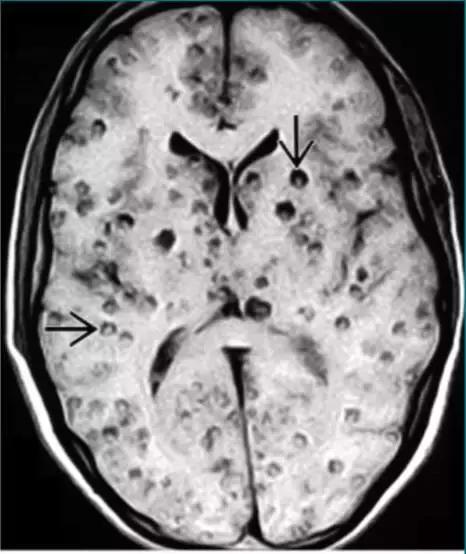

神经脑囊虫病